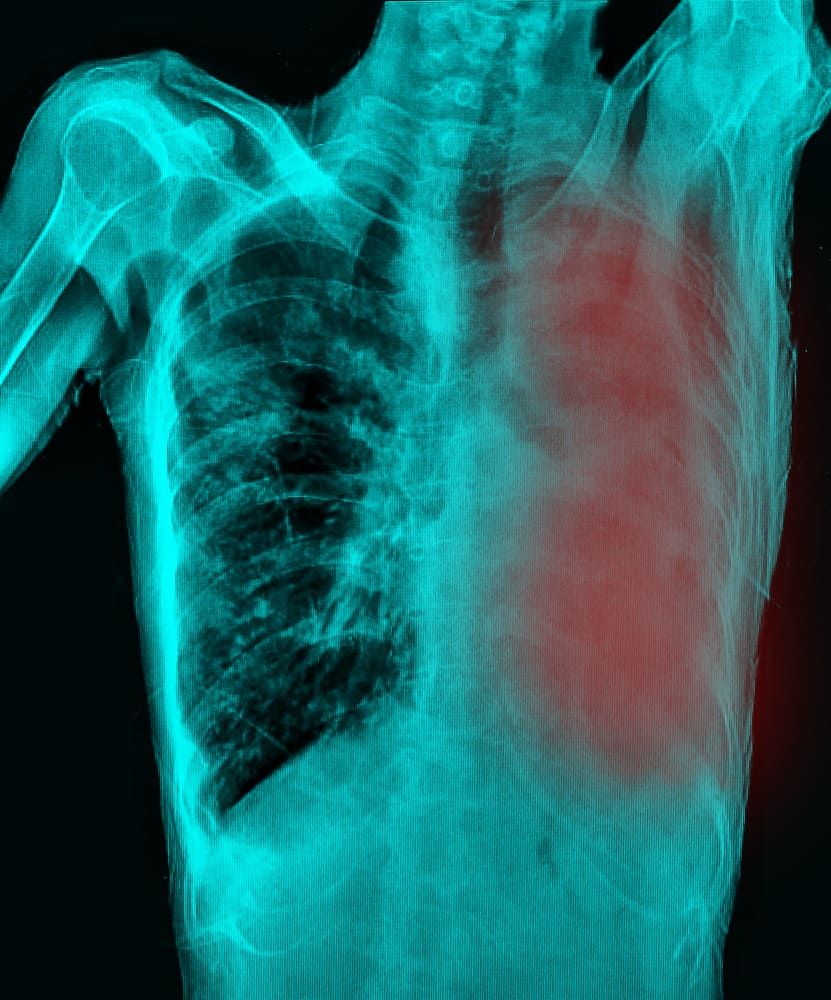

Umumnya, efusi pleura dapat diketahui dari pemeriksaan di dokter. Dokter akan menanyakan riwayat penyakit dan gejala-gejala yang Anda alami.

Setelah itu, biasanya dokter akan melakukan pemeriksaan fisik dengan menggunakan stetoskop atau mengetuk dada Anda.

Efusi pleura membuat udara yang masuk ke dalam paru-paru jadi berkurang. Jika saat pemeriksaan dokter dapat mendengar suara mendecit atau bergesek, kemungkinan besar pleura pada paru-paru telah dipenuhi cairan.

Beberapa tes lainnya juga kemungkinan dilakukan oleh dokter untuk mengetahui seberapa banyak penumpukan cairan pada paru-paru, seperti:

Tes ini biasanya dilakukan untuk melihat apakah ada cairan di pleura. Apabila ada, dokter akan mengarahkan pasien untuk berbaring miring, tergantung bagian tubuh mana yang mengandung lebih banyak cairan.